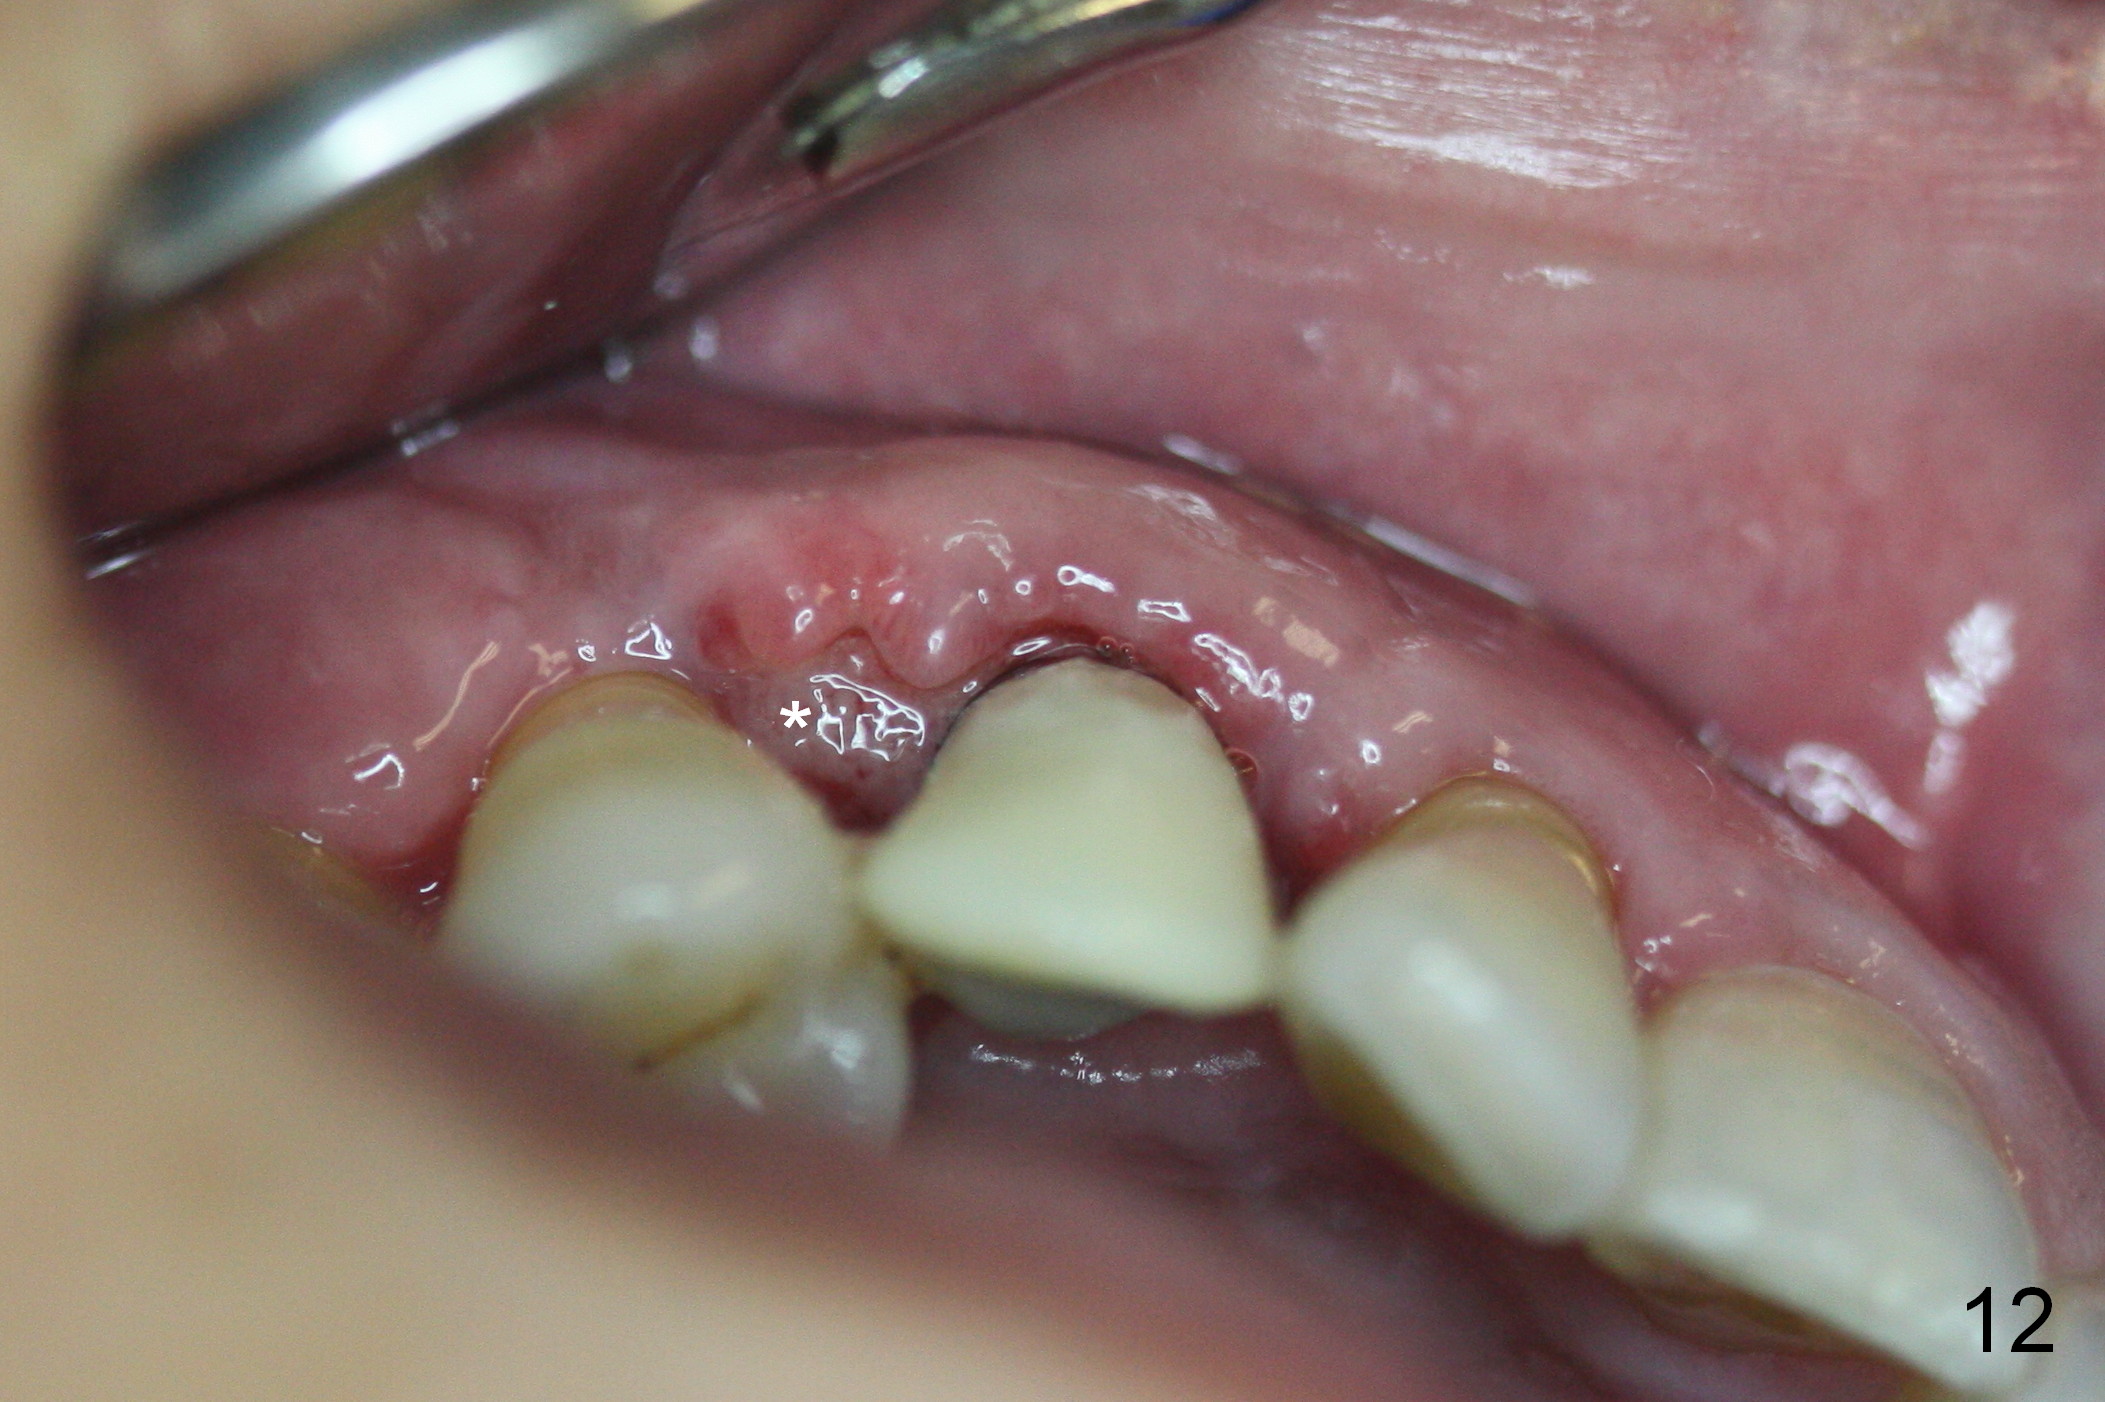

Four months post implant placement, the immediate provisional (Fig.1 P) has mobility with tenderness and perforation at the cervix (^). When the provisional is removed, the buccal plate bulging is more evident (Fig.2 arrowheads). The latter is apparently caused by bone expansion associated with implant placement (Fig.3 black *), since the bulging is not so obvious in a preop CBCT 3 D image (Fig.4 *). There is a layer of fiber granulation tissue (Fig.3 white *) around the mobile implant (I). More fiber tissue is noted when the implant is removed (Fig.5). A new osteotomy is created in the palatal wall of the existing implant site with 2 mm pilot drill, followed by 2.5 and 3 mm reamers. As a 4.5x17 mm tap is being inserted (Fig.6 T), it is deviated buccally. Reamers are re-used to try to remove more palatal bone to let the implant be placed more palatally. When a 4.5x17 mm tissue-level implant is placed (Fig.7,8 I with insertion torque >60 Ncm), there is a small buccal gap (Fig.8 *). A 20° angled abutment (Fig.7,8 A) is placed. An immediate provisional is fabricated with cosmetic satisfaction.

The patient complains of bad smell from the operative field 7 days postop. The wound is gapping with pseudo membrane, which is re-epithelized 14 days postop (Fig.11,12 *) with disappearance of the bad smell.